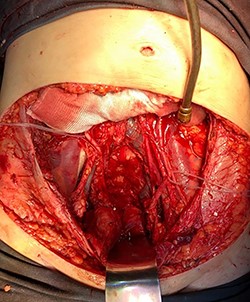

In April 2020, the surgery was performed, with pan-hysterectomy, excision of the AW and skin, pelvic peritonectomy, cecectomy (due to local involvement), partial cystectomy, Hartmann rectosigmoidectomy (Figs 4 and 5), followed by AW partial closure and an intraperitoneal onlay mesh (Open IPOM) in a bridged position with Bard Mesh/BD Sepramesh. Abdominoplasty was performed to allow skin coverage (Figs 6–10). The patient stayed in hospital for 18 days and presented urinary retention. Definitive anatomopathological was HGSC, infiltrating uterus, AW, cecum, rectosigmoid and obturator lymph node metastasis. After cytoreduction, she underwent chemotherapy (carboplatin plus docetaxel).

Pelvis after tumor excision, peritonectomy and lymphadenectomy.